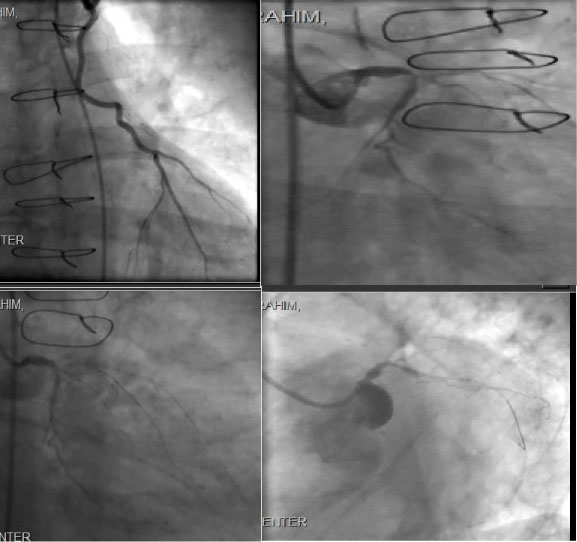

Then we proceeded with diagnostic coronary and graft angiography which showed occlusion of native vessel LAD, RCA, subtotal distal left main (LMN) and ostial left circumflex (LCX) as well as occluded SVG to OM & occluded SVG to RCA, he had patent LIMA to LAD supplying Collateral to posterior descending artery, moderate left Subclavian artery 40%-50% disease (Figures 3). So ad hoc PCI was done to distal LMN into LCX angioplasty and stenting using drug eluting stent (DES) 3.5 × 18 mm with excellent result and TIMI III flow and with improved collateral flow to distal RCA posterior and lateral ventricle circulation (Figures 3).

Figure 3: Patent LIMA to LAD, Subtotal distal LMN and ostial LCX, Left Main and Circumflex Coronary Artery Post Angioplasty/stent. View Figure 3